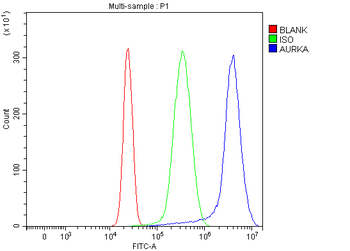

50 μl, 100 μl, 200 μlAnti-Aurora A/AURKA Antibody [orb1290027]

ELISA, FC, IHC, WB

Human

Rabbit

Polyclonal

Unconjugated

10 μg, 100 μgChemerin Rabbit Polyclonal Antibody [orb156351]